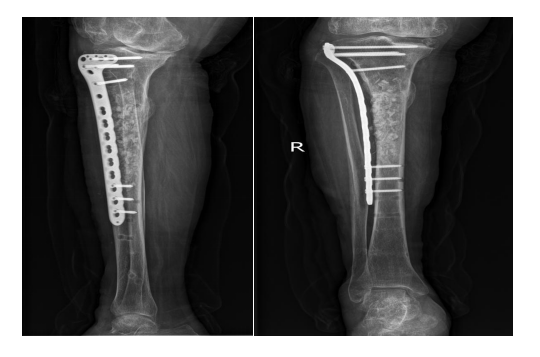

术后经随访复查见骨折断端愈合可,未见明显感染征象。于20232月返院按计划实施3治疗方案:骨水泥取出术、取右髂骨植骨术、人工骨植骨术+钢板、螺钉再固定术。

为什么负压引流【前沿技术】负压封闭引流联合Masquelet技术治疗“不死癌症”——骨髓炎_https://www.jmylbn.com_新闻资讯_第7张